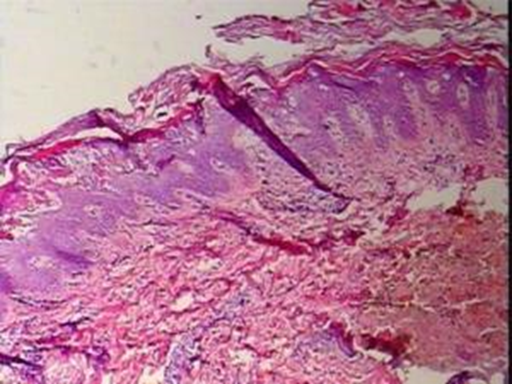

This study reports a case of a 2-year-old female child who presented with recurrent erythema and blisters on the trunk and limbs since birth. As the disease progressed, the original lesion areas gradually developed diffuse light red patches covered with ichthyosiform scales. Histopathological examination revealed characteristic changes including irregular epidermal hyperplasia, focal thickening of the granular layer, and intercellular edema of spinous cells, consistent with the typical pathological manifestations of BCIE. The in-depth study of this case provides important clinical data for understanding the disease pathogenesis.